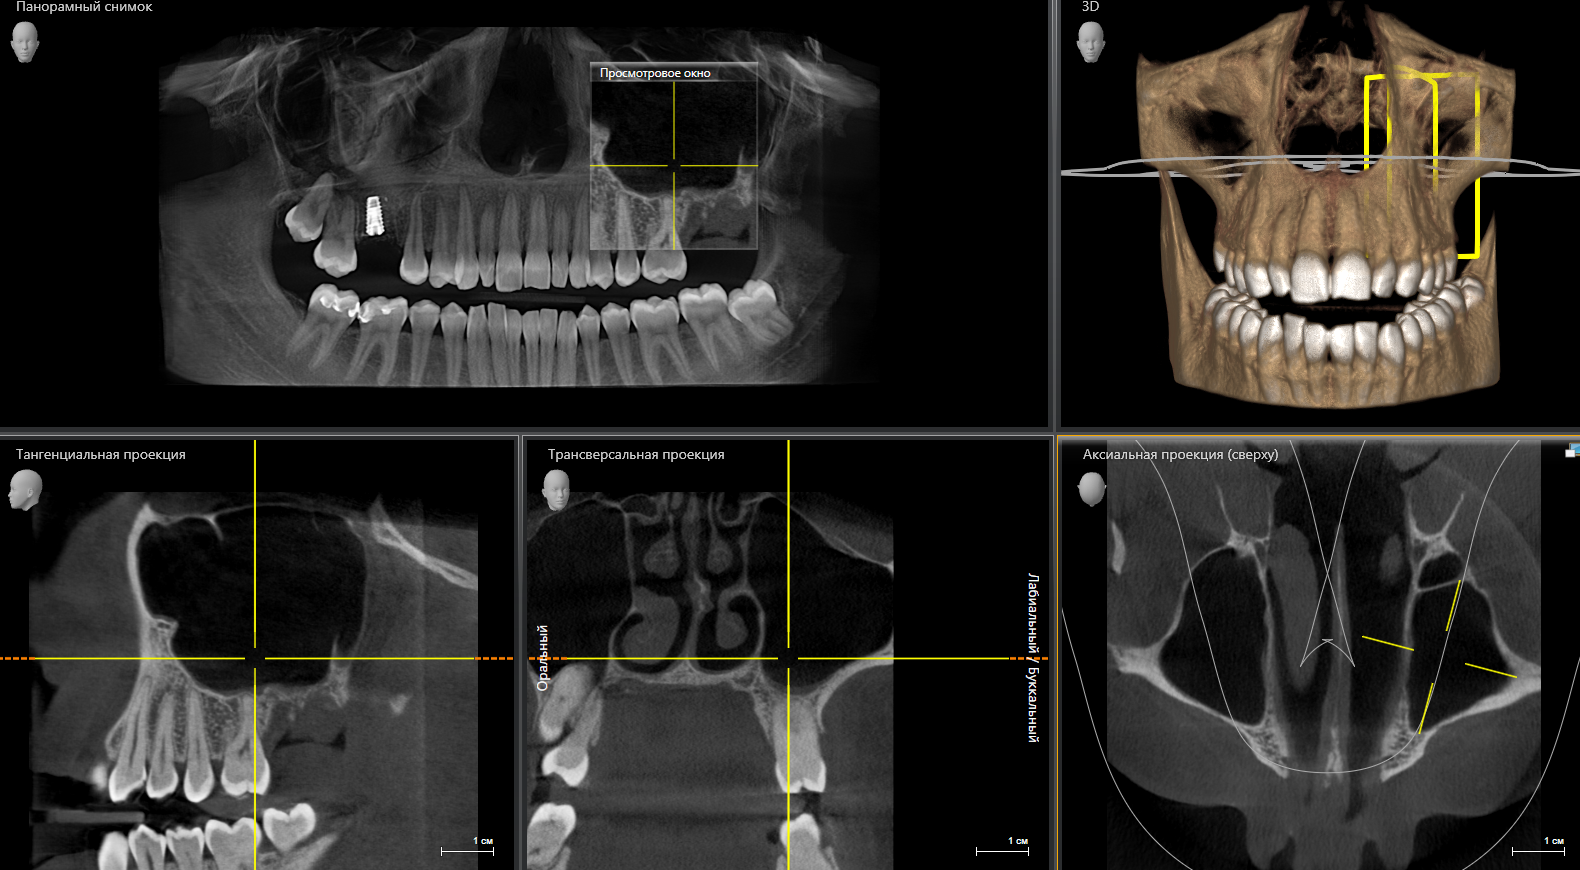

Что вы получаете в итоге? Не просто диск, распечатку или отправку на электронную почту. Вы получаете стопроцентную уверенность. Уверенность в том, что план лечения имплантации составлен идеально, что все каналы будут пройдены до конца, а «зуб мудрости» удалят аккуратно, не задев важные нервы.